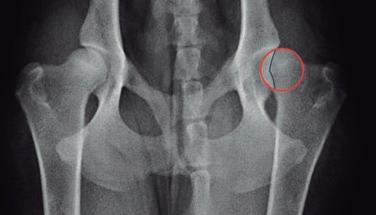

Displasia de cadera (I): etiopatogenia, signos clínicos y pruebas diagnósticas 26